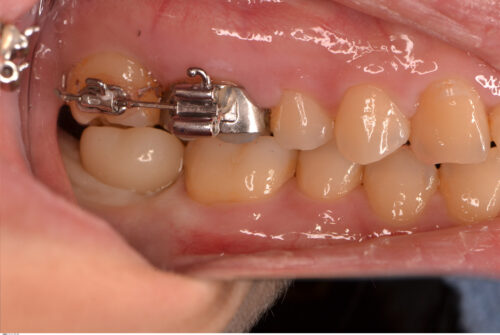

上部構造を装着しました。

最近はインプラント治療を否定する歯科医は少なくなったと感じますが、単純にインプラント治療を良い悪いで決めるのではなく、多角的な視野で判断することが大事だと考えています。